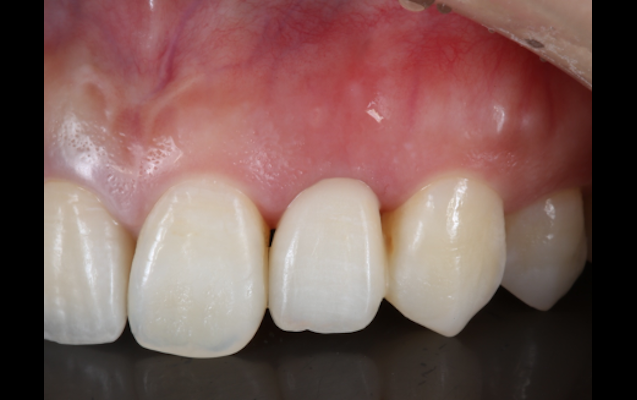

「歯冠長延長術(クラウンレングスニング)」は、歯肉を切開し、歯を支える骨(歯槽骨)を削ることで、治療が必要な部分を露出させる方法です。虫歯等が進行し、歯ぐきが覆いかぶさった状態になってしまっている場合に、歯ぐきを少し下げ治療を施すものです。

歯ぐきを上に露出させることで、精密な印象採得や、細菌感染の起こしにくい環境を作り、結果として長持ちさせる治療が可能となります。

(実際の症例)